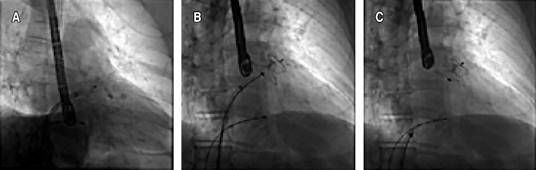

Even though conventional scores showed a low-risk result, it was considered essential to revert to sinus rhythm due to the strong thrombotic component conditioned by the UC and the contraindication for anticoagulation. An electrophysiological study was performed, followed by cryoablation of the four pulmonary veins (Figures 1 and 2), without achieving sinus rhythm, so it was decided to perform non-success electrical cardioversion twice (200 joules). The intervention team decided to perform a wide antral circumferential ablation (WACA) with posterior wall and left atrial appendage isolation, thus successfully achieving arrhythmia jugulation. Due to the hindrance of anticoagulation, after the left atrial appendage isolation, a closure device was placed in the left atrial appendage (Figures 2 and 3). After three months of optimal medical management with apixaban and amiodarone, the patient remained in sinus rhythm, and anticoagulation was discontinued. The patient is free of thrombotic and bleeding events for more than one year after the procedure and after stopping the anticoagulant.

Figure 2: Transesophageal echocardiogram sequence of procedure. A) Transeptal puncture. B) Left atrial appendage ablation. C, D) Positioning of left atrial appendage closure device.